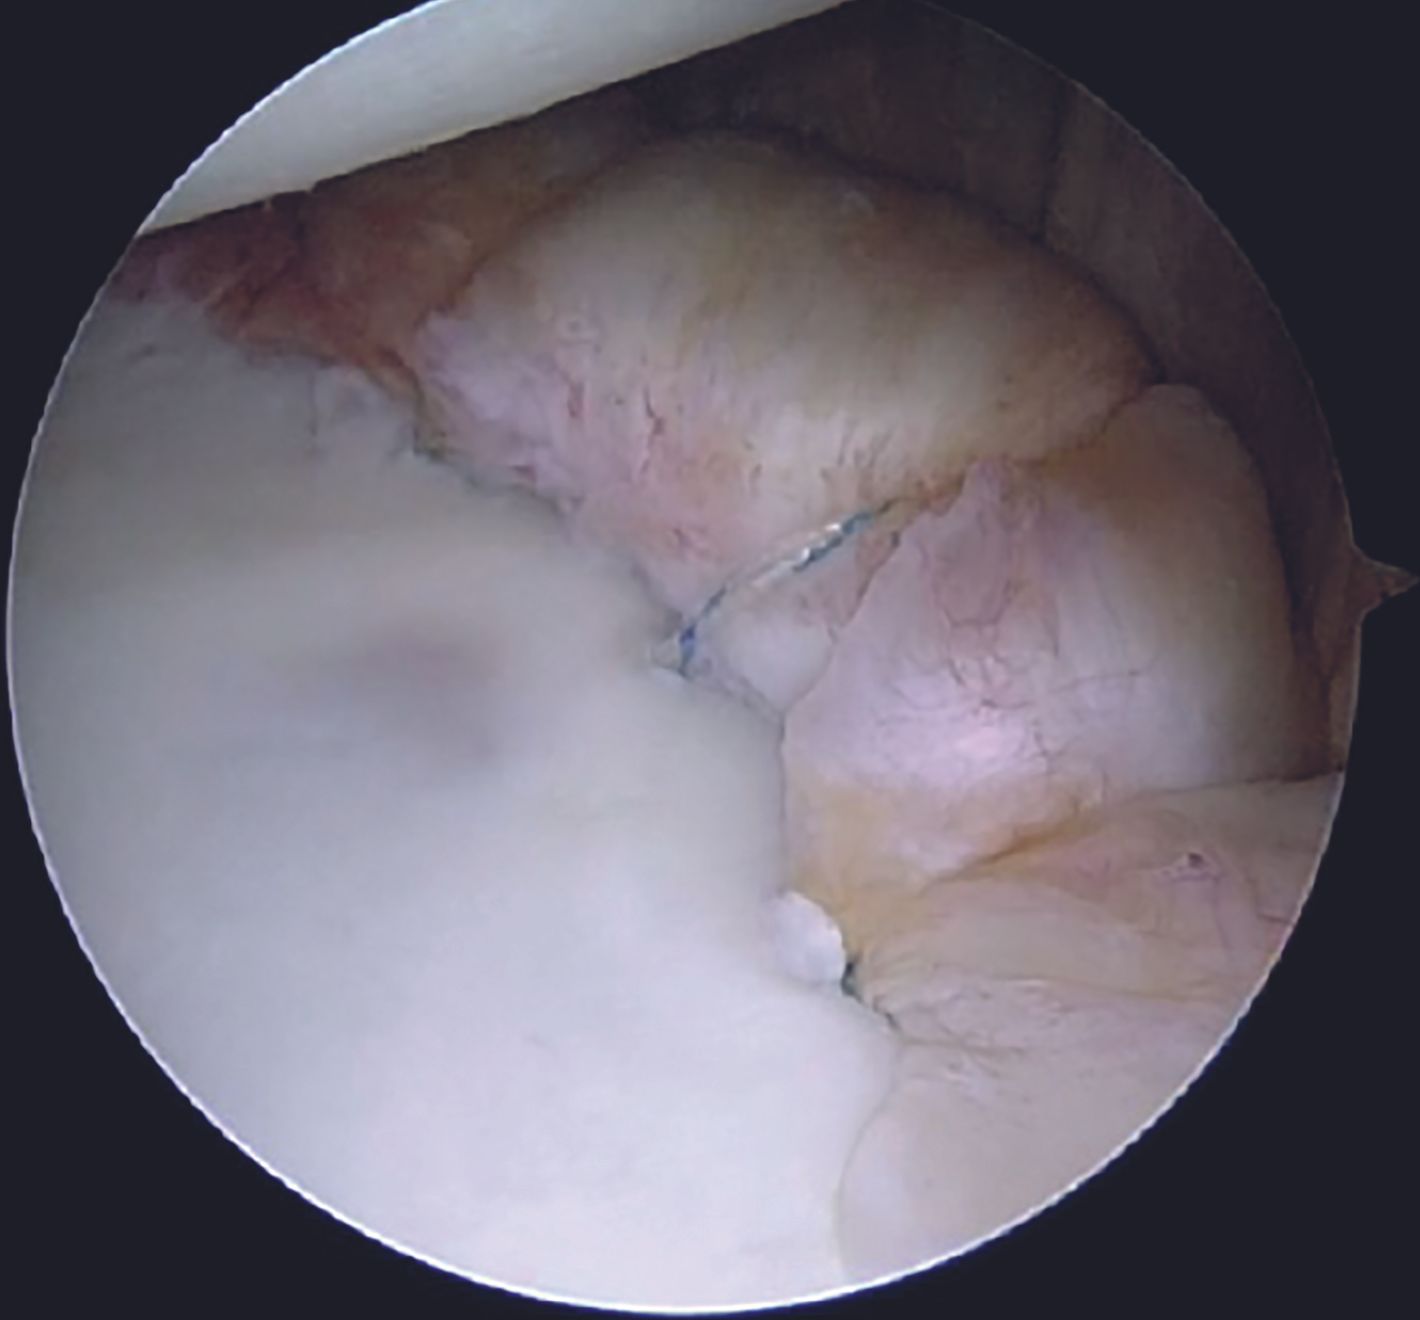

A grasper can be utilized for holding the labral tissue in order to allow easy passage of the suture passer device. With both the tapes in the AI portal, a sliding Duncan loop knot is first tied (Figure 14), followed by at least three half hitches.

Care is taken to keep the knots away from the face of the glenoid by using the shuttled tape as a post and the other one as a throw. Before tying the sliding knot, utmost attention should be paid to provide adequate tension to the labral tissue by pulling the labrum superiorly with a grasper. Tapes are cut with an arthroscopic cutter around 4 to 5mm distal to the knot. One anchor each is placed at 4 and then at 3 O'clock position following a similar steps. After completion of the repair (Figure 15, 16), its integrity and stability is confirmed with a probe. After a thorough wash, closure is done with mattress sutures using 3-0 Ethilon.